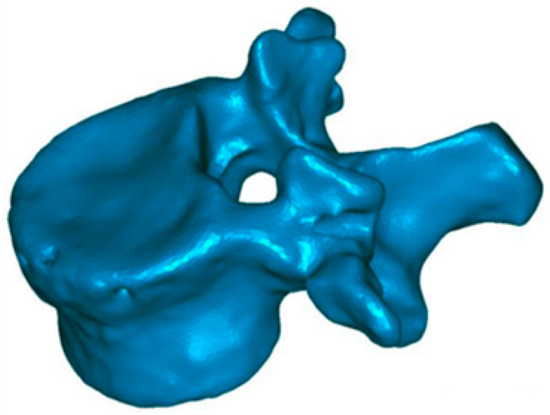

2.2. Evaluation of Anatomical Restoration

To know the vertebral height restoration in fractures after vertebroplasty, there exists no unanimous methodology. Moreover, existing methods are imprecise and can lead to great variability. Therefore, it is necessary to define a method that can be used to evaluate anatomical restoration. In our study, we have used 3D technology, that is definitive in this proposed new treatment [12,18,37]. The method has been developed by LBM ENSAM (Paris, France) to quantify the anatomical restoration. The exploration and interventions were carried in the Hospital Clínico Universitario de Valladolid. We have used a system: Revolution General Electric spectral CT, Healthcare. The protocol to be followed was based on the following parameters: tube voltage: between 80 and 140 kVp, milliamperage: 190 mA, rotation time: 0.8 s, pitch: 0.516, slice thickness: 0.625 mm, ASIR-V-40%, ASIR-V-40% and ASIR-V-40%. From millimetre axial slices of CT scans, 3D reconstructions were obtained using a segmentation technique (Figure 1 and Figure 2).

This method has been validated previously [38,39,40]. It permits comparing, in 3D, two vertebral reconstructions. Once the two 3D reconstructions were obtained for the same vertebra, before and after the intervention, they were superimposed (Figure 3). The posterior arch was affected by neither the VCF nor by the surgical procedure. The two 3D reconstructions are compared by calculation of the distance between the same point belonging to the vertebral body surface. These calculations can be presented by color-coded 3D mappings, in that the calculated distance is represented for any point with a specific colour depending on the measured value.

The precision of the measurements depends on the thickness of the tomography slices. In our application, each 3D reconstruction was obtained using millimetric slices, with a precision of ±1 mm. These 3D reconstructions also make possible to quantify the vertebral angular changes between the two endplates, without any bias. Therefore, based on the 3D reconstruction, the sagittal vertebral kyphosis angle was determined using the projection of the two vertebral endplates in the sagittal plane.